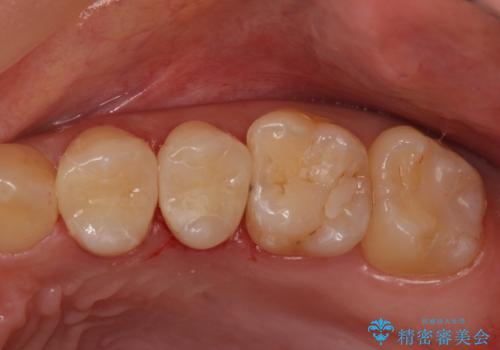

銀歯のやり替え セラミックで白い歯に

銀の詰め物を白い物にしたい